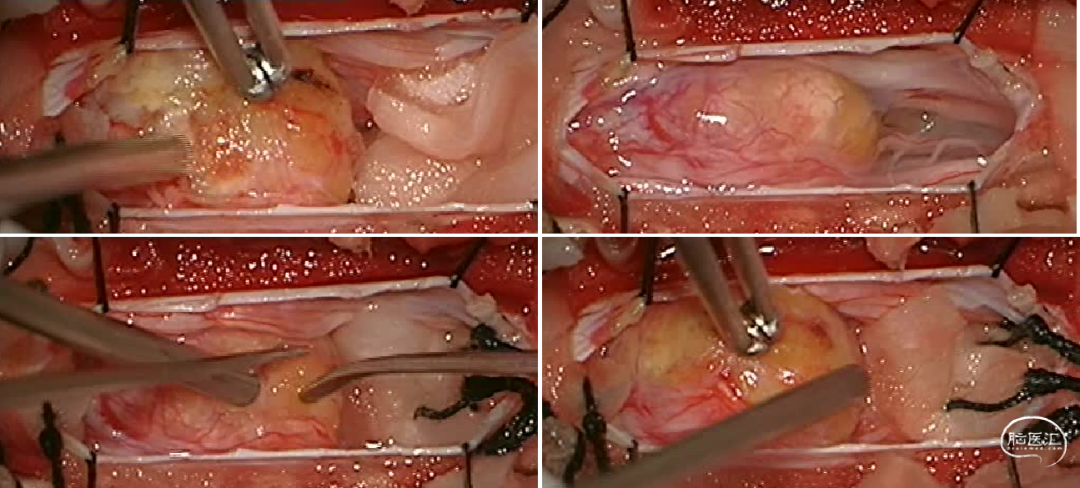

陈卓鹏医师在内镜和显微镜中的协助为手术的顺利完成提供了帮助。肿瘤挤压脊髓圆锥,与其及马尾神经根粘连紧密,显微下切除视野直视下肿瘤,内镜辅助下予以切除肿瘤两端,马尾神经根完好保留,内镜下操作直视外部分肿瘤,减少对神经根的牵拉,降低了术后患者不适发生的机率。术后患者腰部下疼痛及肢体活动障碍症状明显改善。